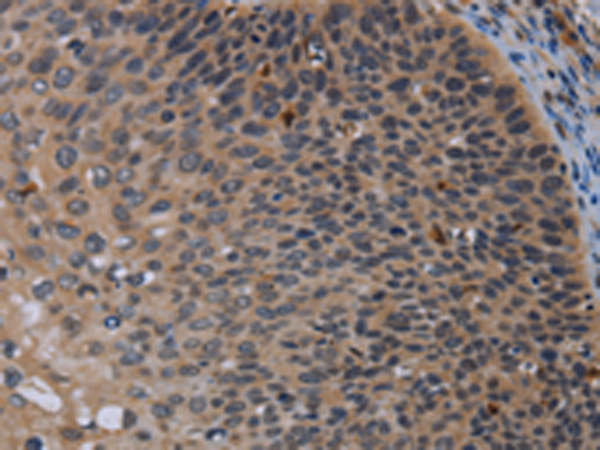

分类: 科研抗体货号: P04997别名: IK1; SK4; KCA4; hSK4; IKCA1; hKCa4; KCa3.1; hIKCa1应用: IHC反应种属: Human